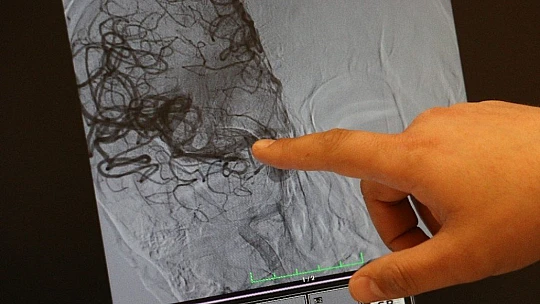

İnme hastalığının yaşla birlikte sıklığı artan bir hastalık olduğuna dikkat çeken Doç. Dr. Aytaç, “Dünyada her 6 saniyede bir kişi inme geçiriyor ve 60 dakikada bir kişi de inmeye bağlı ölüm görüyoruz. 70 yaş civarında binde 20 sıklıkla görülüyor. 45 yaş civarına kadar bu hastalığı görebiliyoruz. Yaş arttıkça sıklığı artıyor ama 20’li yaşlarda da görebiliyoruz. İnme hastalarına erken müdahale ile hastaların felç kalmasına veya ölmelerini engellemeye çalışıyoruz. Merkezimiz bünyesinde erken dönemde damar tıkanıklığıyla gelen hastalara hızlıca müdahale ediyoruz, hastayı hemen anjiyo ünitesine alıyoruz. Tıkalı beyin damarını tespit ettikten sonra o damarın açılmasını sağlıyoruz. Böylelikle hastaların felç kalmasını engelliyoruz ki inme, dünyada sakat bırakma ve engellilik konusunda birinci sırada yer alan en önemli hastalıklardan bir tanesidir ve dünyadaki ikinci en sık ölüm nedeni inmeye bağlı ölümler oluşturuyor. Merkezimiz de yaklaşık 2017 yılından beri bu bölgedeki hastalara hizmet vermekte. Bugüne kadar yaklaşık 500 anjiyo işlemi gerçekleştirdik ve yüzlerce hastanın hayatına dokunabilme imkanımız oldu. Sadece erken dönemde inme hastaları değil aynı zamanda inmeye neden olan şah damar tıkanıklığı olan hastalara da stent takarak hastaların uzun dönemli inme geçirmelerini veya daha ağır bir inme geçirmesini engelliyoruz” dedi.

İnme belirtileriyle gelen ve sağlığına kavuşan iki hasta hakkında da bilgi veren Doç. Dr. Aytaç, "İnme hastalarında bizim için en önemli olay, zaman. Zaman bizim için çok önemli ki hatta ‘zaman eşittir beyin’ diyoruz. Biz bu hastalara ne kadar erken müdahale edersek o kadar hastaların sağ kalmasını sağlıyoruz. Kabaca hastanın ağzında kayma, konuşmasında bozulma, kol ve bacağında kuvvetsizlik, uyuşma ve denge kaybı gibi şikayetler inmenin erken bulguları olabilir. O yüzden evden zaman geçirmeden, suya ve duşa sokma ve sarımsak yedirme gibi işlemler ki toplumumuzda en fazla bu tür işlemler yaptırılıyor, bu tarz yanlış işlemler yapılmadan bir an önce hastaların 112 vasıtasıyla ilgili merkezlere gelmesini önemle tavsiye ediyorum. Murat bey, sol tarafında kuvvetsizlik şikayetiyle geçen ay gelmişti. Hastamızın sol kol ve bacağı tutmuyordu, konuşmasında bozulma olmuş ve bilinci tama yakın kaybolmuştu. Hastayı hemen hızlıca tomografi çektikten sonra hastanın ana damarında tıkanıklık olduğunu tespit ettik, hastayı anjiyo ünitesine aldık ve tıkalı damarı özel geri alınabilir stent sistemiyle pıhtıyı çıkardık. Hastanın tutmayan sol kol ve bacağının tekrar hareketlendiğini gördük. Bu vasıtayla Murat bey tekrar eski sosyal hayatına, işine geri dönebildi. Diğer hastamız da bize geçen aylarda gelmiş bir hasta o da aynı şikayetle geldi ve tamamen hareket edemez durumdaydı. İki hastamız da bize erken dönemde, ilk bir saat içerisinde geldi. Her iki hastamızı bir saat içerisinde anjiyoya aldık ve tıkalı olan beyin damarlarını açtıktan sonra çok şükür her iki hastamız da sosyal hayatlarına devam edebildi” diye konuştu.